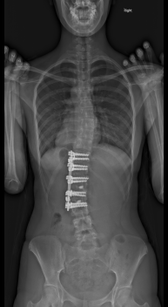

思春期特発性側弯症の全脊椎レントゲンで背骨が大きくSの字に曲がっています。最も曲がっている箇所は80°で、高度側弯に分類されます。後方からの脊柱側弯矯正術で真っ直ぐになっています。

以前はこのフラットバック(生理的胸椎後弯の消失)を治すことは困難でしたが、当院では手術方法の様々な工夫により生理的胸椎後弯の復元を行っております。この症例は術後に胸椎後弯角が26°と改善しており、生理的な胸椎後弯が形成されています。さらに頸椎後弯にも良い影響を及ぼし、術後は頸椎前弯化が得られつつあるのが分かります。(黄色矢印)

他、側弯変形は必ず大なり小なりの回旋変形を伴います。脊柱の回旋変形は胸郭(肋骨)の回旋につながり、これにより側弯の患者さんは背中の片方が出っ張っています(多くは右)。リブハンプと言いますが、脊柱変形矯正によりこの回旋変形も改善します。この症例も術前に肋骨がかなり隆起していますが、術後にこの隆起がかなり減じているのが分かります。(赤矢印)